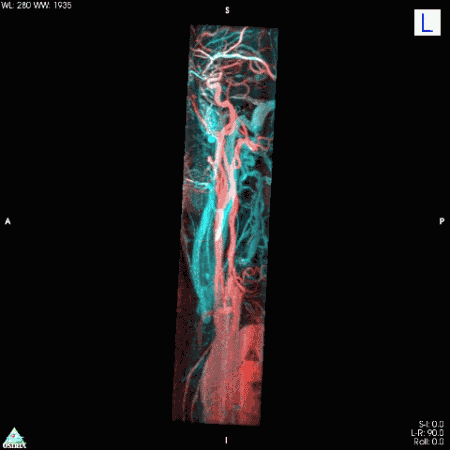

彩色核磁共振下的人体主动脉彩色核磁共振下人体的静脉和动脉,一目了然